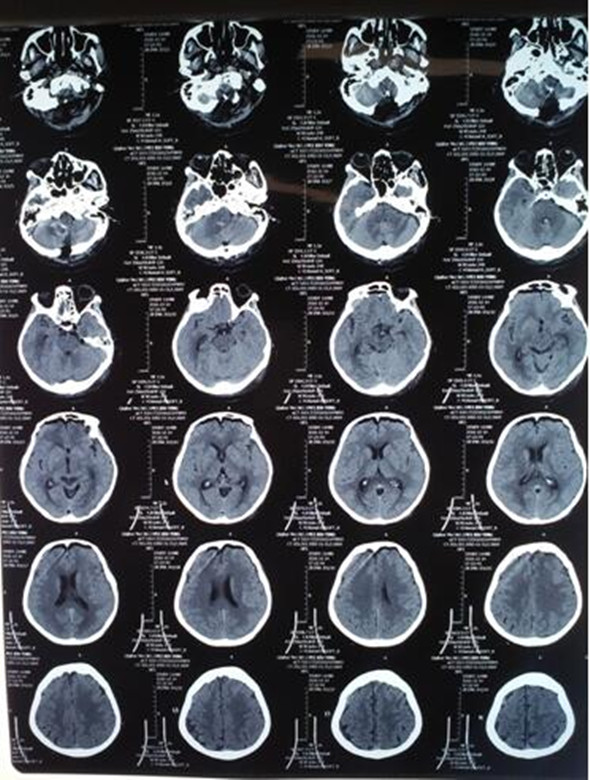

手术如期开始,探望患者、术前沟通、剃头、备手术用品、备血……工作有条不紊进行。经麻醉医生麻醉后,吴卫东主任为患者采取俯卧位后颅窝开颅,术中发现患者右侧小脑后下动脉2mm大小动脉瘤破裂出血,分离、夹闭……每一个步骤都非常谨慎,连呼吸都变得小心翼翼。吴卫东主任凭借精湛的手术技能,在高风全副主任、麻醉科医师的默契配合下,最终,成功将动脉瘤完全夹闭,第一时间挽救了患者的生命,手术圆满成功。术后第一天,患者意识清醒。现患者已正常活动。

术后第一天头部CT